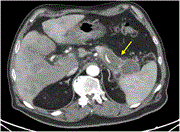

Undifferentiated embryonal sarcoma of the liver: a case report of a rare case in an adult patient

Ana M Marques and others

Journal of Surgical Case Reports, Volume 2023, Issue 10, October 2023, rjad578, https://doi.org/10.1093/jscr/rjad578